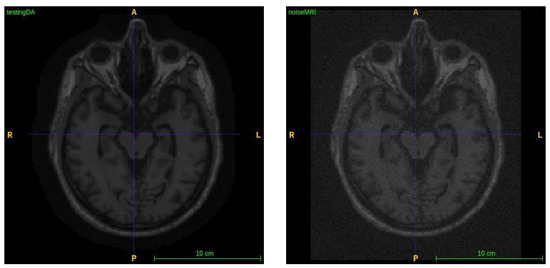

3.2. Image Fusing and Preprocessing

4.3.1. Image Fusion Performance